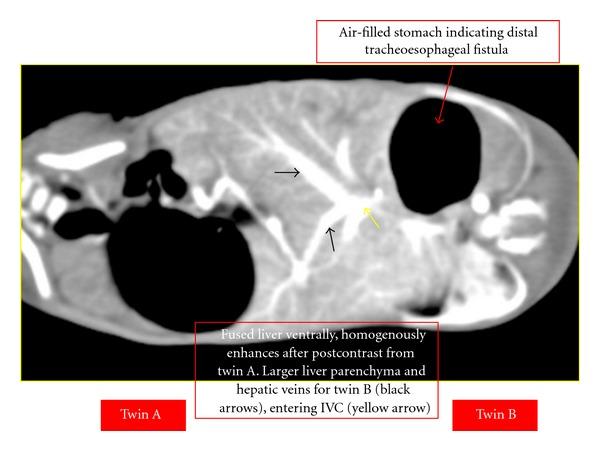

Conjoined twins are rare and present a unique challenge to pediatric surgeons and radiologists. An imaging strategy to accurately define anatomic fusion, vascular anomalies, and other associated abnormalities is important for surgical planning and prognostic information. A conjoined female twin with a combined weight of 2.8 kg was born by emergency caeserean. Hence, a computed tomography scan of the thorax and entire abdomen at 1.25 mm slice thickness was performed to delineate the internal structures of the twins. CT-angiography defined specific vascular supply which determined the distribution of shared structures between the twins. An echocardiogram showed four heart chambers with atrioventricular septal defect. To further evaluate the heart chambers, the twin was planned for gated cardiac magnetic resonance imaging. Unfortunately, they succumbed 6 hours apart due to complication of septicemia. Magnetic resonance imaging and CT scan provide excellent anatomic detail, demonstrating organ position, shared viscera, and limited vascular anatomy, whilst angiography defined specific vascular supply, useful in determining the distribution of shared structures between the twins in planning for surgery.